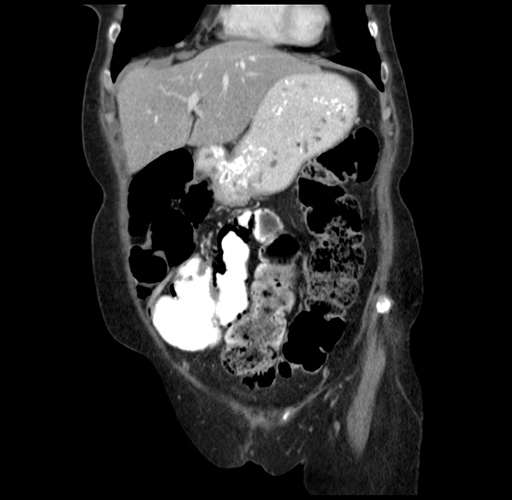

Coronal Venous